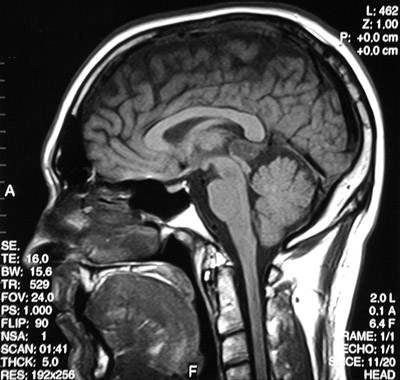

In the sagittal T1 weighted MRI scan above there is mass lesion in the region of the pineal gland. This is a pineocytoma. Below this mass appears bright in axial view post gadolinium injection.